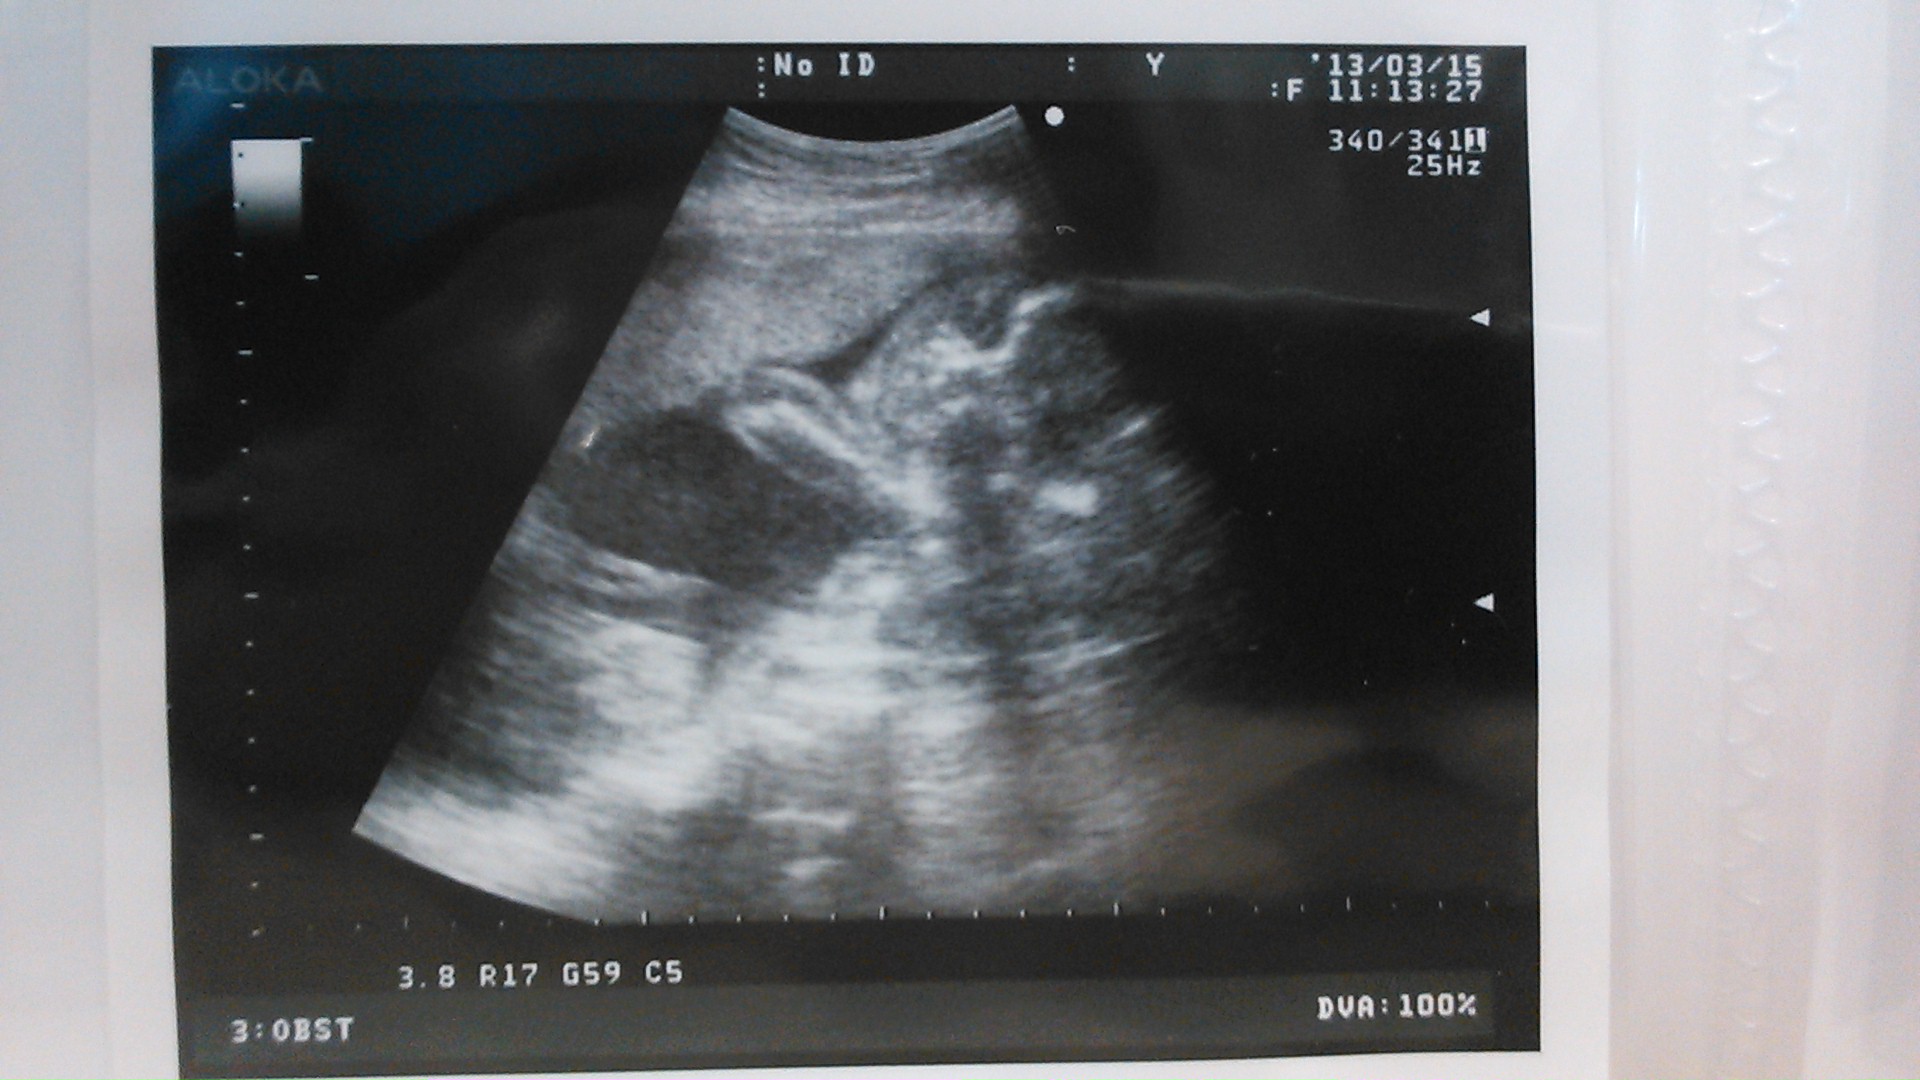

echo